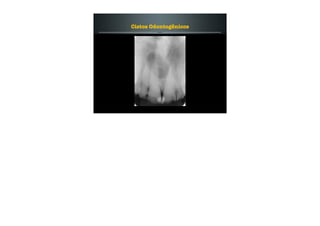

Cisto do Ducto Nasopalatino

Acredita-se que o cisto origina-se de remanescentes

embrionários do ducto nasopalatino (estrutura que liga a

cavidade nasal à oral, na região de canal incisivo).

Mais comum entre a quarta e sexta década de vida.

Geralmente assintomático, porém pode causar tumefação

em palato e dor.

Radiograficamente apresenta-se como uma área

radiolúcida bem circunscrita, próximo a linha média da

região anterior da maxila, entre os ápices dos incisivos

centrais.

Em geral a lesão é arredondada, porém quando atinge

grandes proporções pode assumir um aspecto que lembra

uma pêra ou um coração.